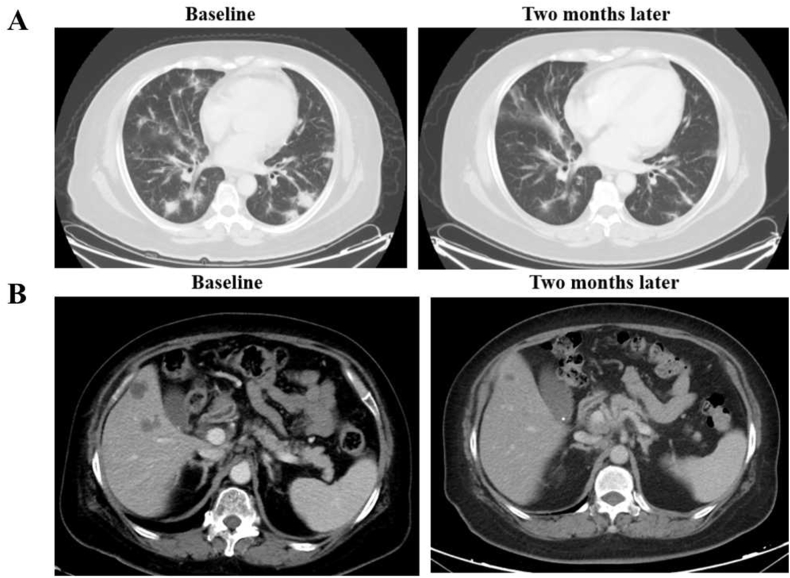

A 63-year-old woman presented with cough and multiple lung masses. Bronchoscopic biopsy revealed lung adenocarcinoma. Tests for common driver mutations such as EGFR, KRAS, ALK, ROS1, MET, and BRAF were negative. Tumor tissues showed high levels of PD-L1 expression (TPS 90%). She was administrated pembrolizumab monotherapy as first line therapy and achieved a confirmed partial response. Five months later, clinical evaluation showed disease progression with an enlarged lung mass. A repeat biopsy of the lung mass showed poorly differentiated adenocarcinoma and PD-L1 overexpression (TPS 70%). We performed NGS with a 1021-gene panel and detected KIF5B-RET fusion. Owing to the unavailability of selective RET inhibitors in China between 2018 and 2020, she received five lines of therapy, including chemoimmunotherapy and anlotinib. She was subsequently treated with the MKI cabozantinib as the seventh-line treatment, which was discontinued a month after initiation because of disease progression in the liver. She took part in the selpercatinib study in China, and imaging indicated a partial response. Thirteen months after selpercatinib treatment, computed tomography showed pleural effusion and enlarged liver lesions. Pleural cytology revealed the presence of adenocarcinoma cells. Molecular testing of the pleural effusion cell-free DNA (cfDNA) revealed KIF5B-RET fusion, KRAS p.A146V mutation, and EGFR amplification with a copy number of 2.1 (Fig. 4).

Fig. 4.

Clinical response of pembrolizumab and selpercatinib for the case with RET fusion and PD-L1 over-expression. A: CT scan revealing the clinical response to pembrolizumab. B: CT scan revealing the clinical response to selpercatinib. Abbreviations: PD-L1: programmed cell death ligand 1; RET: rearranged during transfection; CT: computed tomography.

Here, we report a case with KIF5B-RET fusion and PD-L1 overexpression that sequentially responded to pembrolizumab, chemoimmunotherapy, and later-line selpercatinib. Following resistance to selpercatinib, pleural effusion cfDNA testing revealed KIF5B-RET fusion, KRAS p.A146V mutation, and EGFR amplification. Currently, limited reports describe resistance mechanisms to selective RET inhibitors. Solomon et al. reported that three patients with RET fusion-positive NSCLC acquired RET G810 solvent-front mutations after selpercatinib resistance [25]. Lin et al. found three patients acquired MET amplification and one acquired KRAS amplification [26]. Preclinical studies showed that activation of the EGFR pathway mediated cancer cells resistance to RET inhibitors [27,28]. Mechanisms of resistance to selective RET inhibitors still need to be explored.